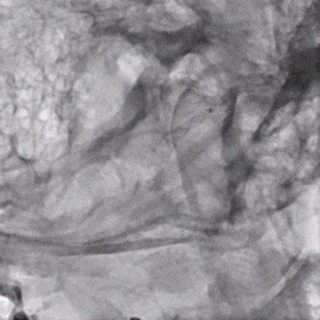

微导丝带017 Accessway微导管上高至远端。

第一枚2*20支架通过017支架微导管到位。

支架远端打开。

支架远端打开情况。

支架中段打开,过50%释放标记点。

造影显示支架整体打开良好。

支架完全释放。

微导管沿推送杆通过支架,撤出推送杆,保留通路。

造影显示支架打开良好,准备桥接第二枚支架。

第二枚3*25支架沿017支架微导管上高。

第二枚支架远端释放。

第二枚支架释放至中段。

中段释放适当推挤系统,保持贴壁良好。

中段释放后造影。

继续释放支架。

继续释放支架,造影观察贴壁良好。

完全释放支架。

支架微导管沿推送导丝上高并将推送导丝撤出。

术后即刻造影。

术后重建。